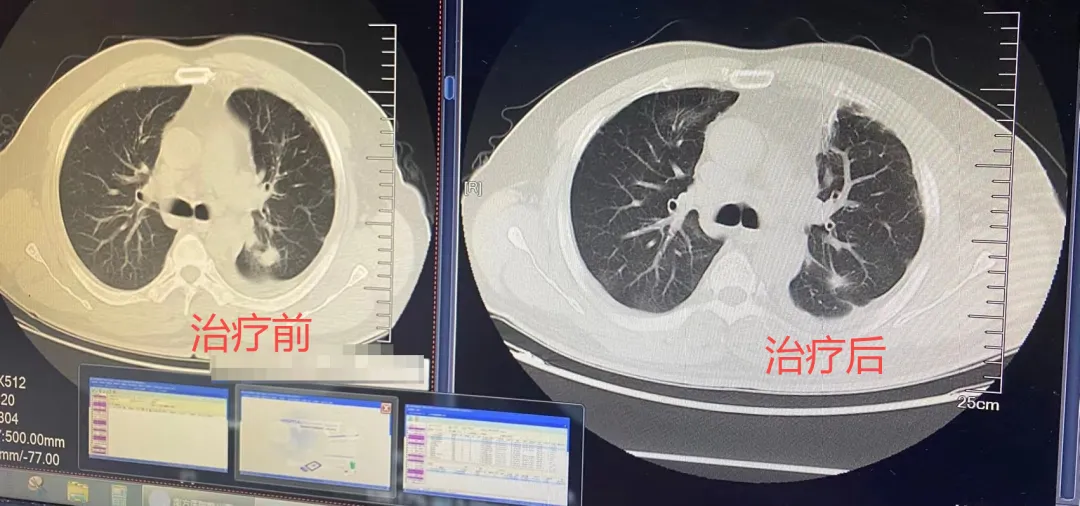

2024 年,17 岁的少年陈捷(化名)因右腿持续疼痛就医,MRI 检查显示股骨下端巨大占位,活检确诊为高度恶性骨肉瘤。更令人揪心的是,肺部 CT 发现双肺散在分布 12 枚转移灶,最大直径达 2.5 厘米 —— 这意味着肿瘤已进入晚期,传统治疗手段预后极差。

治疗第 2 个月复查显示,肺部转移灶开始出现中央空洞化;第 4 个月,CT 扫描证实所有肺结节完全消失,原发肿瘤体积缩小 83%。这一结果远超预期,为保肢手术创造了条件。术中冰冻病理显示,肿瘤组织 95% 以上呈坏死改变,切缘阴性。术后继续巩固治疗 3 个月,患者目前已恢复正常生活,复查肿瘤标志物持续阴性。